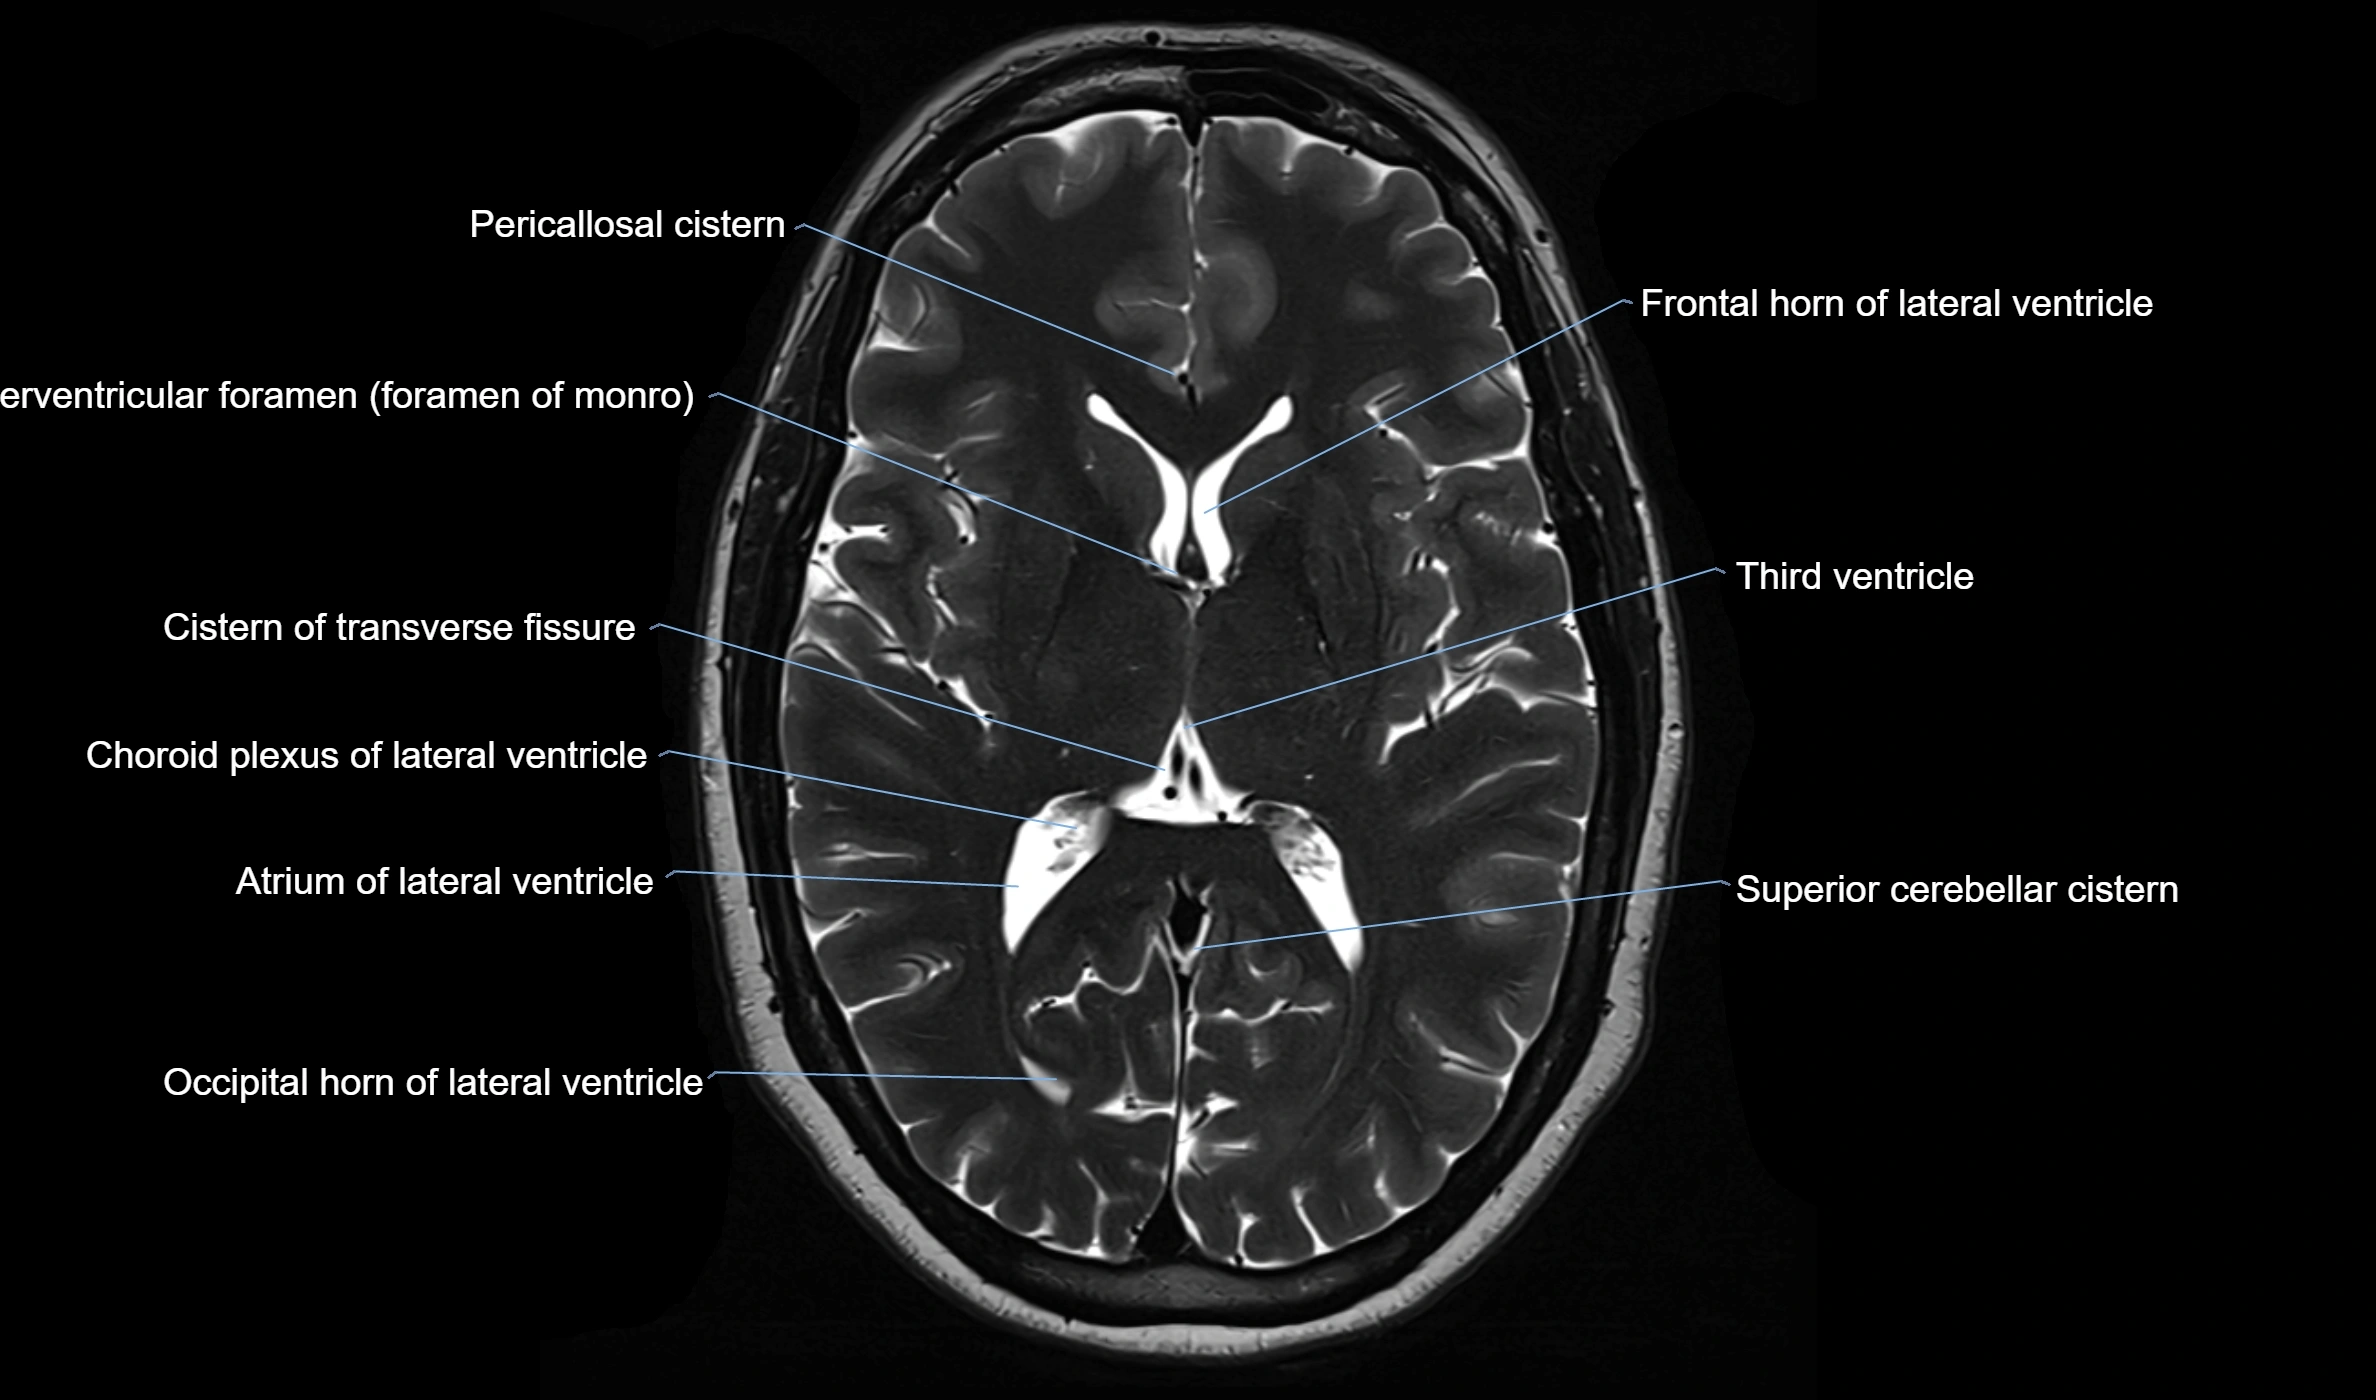

CT image

image